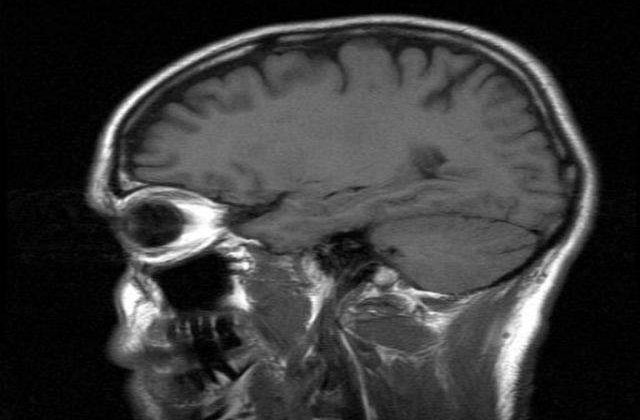

Virusul ar putea creste riscul de a suferi de Alzheimer din cauza ca batranii au un sistem imunitar slabit, care creaza oportunitati pentru ca virusul sa ajunga la creier, potrivit noilor cercetari. Odata ajuns in creier, virusul poate declansa procesul care in cele din urma duce la aparitia bolii Alzheimer: formarea de placi care duc la intreruperea conexiunilor neuronale si, in cele din urma, la moartea celulelor nervoase. Acest proces provoaca pierderi de memorie si o micsorare a capacitatii intelectuale, simptome caracteristice bolii Alzheimer, scrie mediafax.

Cercetarile anterioare au aratat ca oamenii care nu se imbolnavesc de Alzheimer produc mai putin dintr-o substanta care formeaza placile senile sau organismul lor este mai bine pregatit pentru a curata aceasta substanta de pe suprafata celulelor.

"Studiul nostru arata in mod clar ca exista o legatura intre infectia cu Herpes simplex de tip 1 si riscul de Alzheimer, ceea ce inseamna, pentru noi, aparitia de noi oportunitati pentru dezvoltarea unui tratament care sa stopeze boala. Ce este foarte interesant legat de aceasta ipoteza este ca in prezent acest virus poate fi combatut cu medicamente antivirale", a spus Hugo Lövheim, de la Universitatea Umea din Suedia, care sustine ca este posibil ca in cativa ani s-ar putea incepe tratarea pacientilor pentru a preveni instalarea maladiei Alzheimer.

Studiul a fost realizat pe 3.432 de participanti a caror stare de sanatate a fost urmarita timp de 11 ani si trei luni, in medie. Savantii au descoperit ca reactivarea virusului dubleaza riscul de Alzheimer.